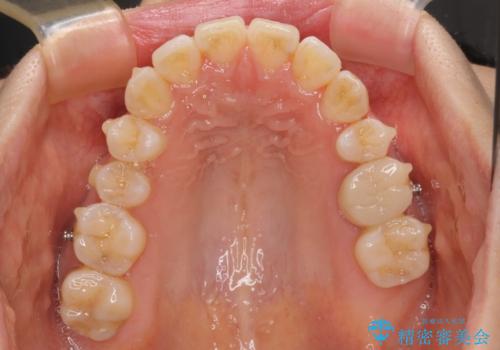

八重歯と開咬の抜歯矯正 ワイヤー装置を併用したインビザライン矯正治療

- 咬み合わない前歯と八重歯などのデコボコを気にして来院された患者様です。

上下前歯の位置を比較すると上顎が前方にあり、デコボコ改善でより上顎が前方に行く可能性があります。

開咬の改善にはインビザラインが有効であり、インビザライン単体での治療を検討しましたが、上顎前突を回避するために上顎左側第一小臼歯抜歯を行うこととしたため、補助装置とワイヤー矯正を併用した上で、インビザラインによる矯正治療を行うこととしました。